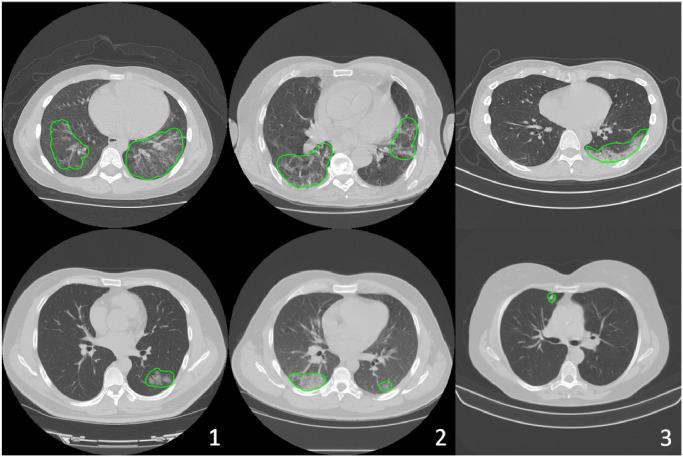

The recent outbreak of Coronavirus Disease 2019 (COVID-19) has led to urgent needs for reliable diagnosis and management of SARS-CoV-2 infection. The current guideline is using RT-PCR for testing. As a complimentary tool with diagnostic imaging, chest Computed Tomography (CT) has been shown to be able to reveal visual patterns characteristic for COVID-19, which has definite value at several stages during the disease course. To facilitate CT analysis, recent efforts have focused on computer-aided characterization and diagnosis with chest CT scan, which has shown promising results. However, domain shift of data across clinical data centers poses a serious challenge when deploying learning-based models. A common way to alleviate this issue is to fine-tune the model locally with the target domains local data and annotations. Unfortunately, the availability and quality of local annotations usually varies due to heterogeneity in equipment and distribution of medical resources across the globe. This impact may be pronounced in the detection of COVID-19, since the relevant patterns vary in size, shape, and texture. In this work, we attempt to find a solution for this challenge via federated and semi-supervised learning. A multi-national database consisting of 1704 scans from three countries is adopted to study the performance gap, when training a model with one dataset and applying it to another. Expert radiologists manually delineated 945 scans for COVID-19 findings. In handling the variability in both the data and annotations, a novel federated semi-supervised learning technique is proposed to fully utilize all available data (with or without annotations). Federated learning avoids the need for sensitive data-sharing, which makes it favorable for institutions and nations with strict regulatory policy on data privacy. Moreover, semi-supervision potentially reduces the annotation burden under a distributed setting. The proposed framework is shown to be effective compared to fully supervised scenarios with conventional data sharing instead of model weight sharing.

最近爆发的 2019 年冠状病毒病(COVID-19)导致对 SARS-CoV-2 感染的可靠诊断和管理的迫切需求。目前的指南是使用 RT-PCR 进行检测。作为诊断影像学的补充工具,胸部计算机断层扫描(CT)已被证明能够揭示 COVID-19 的特征性视觉模式,在疾病过程的几个阶段都具有明确的价值。为了方便 CT 分析,最近的努力集中在使用胸部 CT 扫描进行计算机辅助特征描述和诊断上,这已经显示出了有希望的结果。然而,跨临床数据中心的数据域转移在部署基于学习的模型时带来了严重的挑战。缓解这个问题的一种常见方法是使用目标域的本地数据和注释来对模型进行局部微调。不幸的是,由于全球各地设备的异质性和医疗资源的分布不均,本地注释的可用性和质量通常会有所不同。在 COVID-19 的检测中,这种影响可能更为明显,因为相关模式的大小、形状和纹理都有所不同。在这项工作中,我们试图通过联邦学习和半监督学习来解决这个挑战。采用一个由三个国家的 1704 个扫描组成的多国家数据库来研究在使用一个数据集进行模型训练并将其应用于另一个数据集时的性能差距。专家放射科医生手动对 945 个扫描进行了 COVID-19 发现的标记。在处理数据和注释的变异性时,提出了一种新颖的联邦半监督学习技术,以充分利用所有可用的数据(有或没有注释)。联邦学习避免了对敏感数据共享的需求,这使得它对数据隐私监管政策严格的机构和国家有利。此外,半监督在分布式设置下有可能减少注释负担。与传统的数据共享而不是模型权重共享的完全监督场景相比,所提出的框架被证明是有效的。